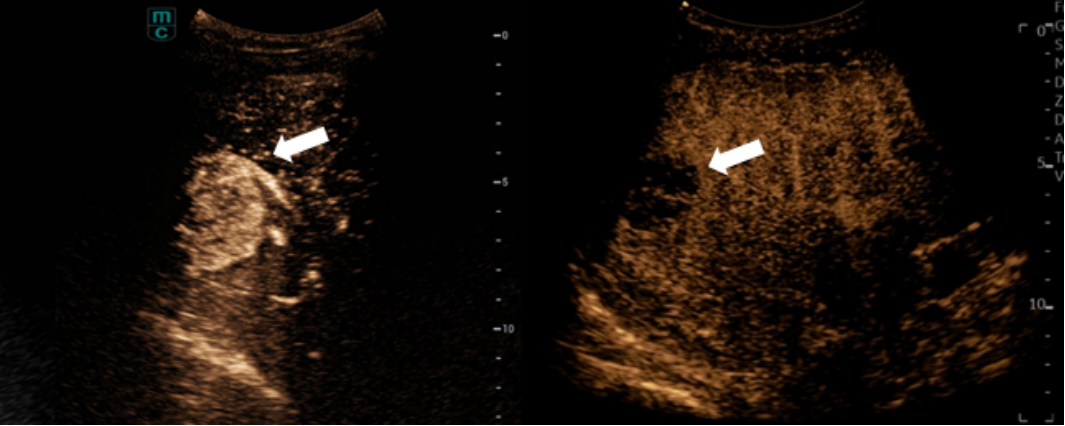

▲病灶(白色箭头)超声造影显像:治疗前明显强化(左图)、治疗后无强化(右图)

组织碎化技术(Histotripsy)是国际上前沿的恶性肿瘤无创治疗新技术,利用高强度聚焦超声准确照射肿瘤组织,在肿瘤内形成的微气泡会迅速膨胀及收缩,继而产生机械冲击波破坏及液化肿瘤细胞,对正常血管及胆管结构无影响,保证了肿瘤治疗的安全性及有效性。整个治疗过程配合先进的超声波造影技术实时精准导航,确保治疗范围聚焦于目标肿瘤,同时减低对周边组织的影响。